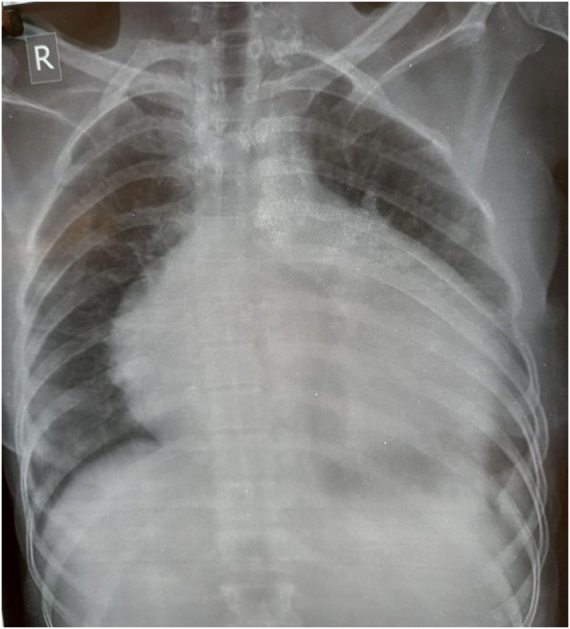

Case presentation: A 50-year-old woman presented with sudden shortness of breath, chest pain, and reduced urine output. Diagnostic tests revealed a large pericardial effusion leading to cardiac tamponade, acute kidney injury, and microangiopathic hemolytic anemia. Clinical assessment and immunological testing confirmed the diagnosis of systemic sclerosis. The patient received pericardiocentesis, hemodialysis, and was treated with diuretics and angiotensin-converting enzyme inhibitors (ACEIs).